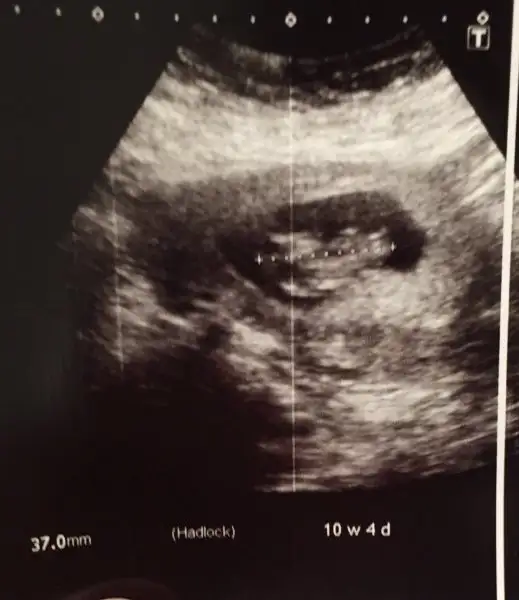

Merhaba teyzeler dün ultrasona girdk bebişimiz maşallah zıplıyordu:dua:

Eklentiler

• 1830C80C-E5C4-49CF-BF0E-63C27D1BDAB3.webp

1830C80C-E5C4-49CF-BF0E-63C27D1BDAB3.webp

13,3 KB · Görüntüleme: 93

Maşallah hareketlendiler iyice bence cumartesi 10+3 te göreceğim inşallah. Ultrason net göstermemiş aslında tam bebeğe benziyor şimdi kuzun

Evet canım aslında gördüğümde kolları bacakları oynuyordu zıplıyordu ama dr iyi açıdan alamamış sanırım usg de pek iyi değil devletti zaten :anneadayı: